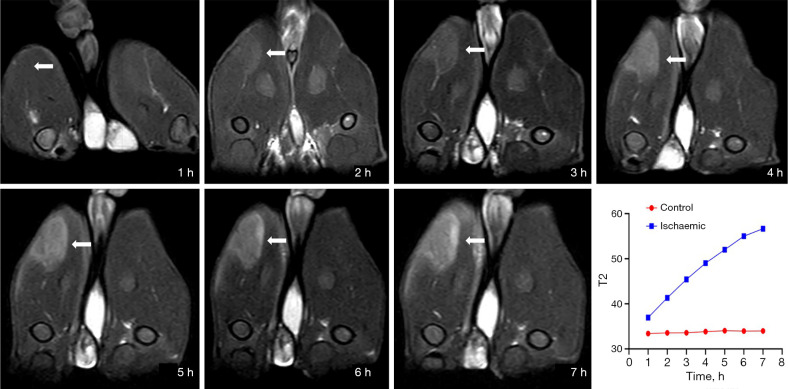

Results: The perfusion fraction (f) of ischemic muscle significantly decreased from 6.19%±1.13% at 1 hour to 2.50%±0.64% at 7 hours (control: 7.19%±1.03%), representing a strong negative correlation with ischemic duration (r=-0.790). The true diffusion coefficient (D) remained relatively stable [(1.41-1.46)×10-3 mm2/s] but was slightly elevated compared to controls. The pseudo-diffusion coefficient (D*) showed a sharp increase at 5 hours [(74.01±5.79)×10-3 mm2/s]; control: [(61.28±9.31)×10-3 mm2/s], followed by a drop at 6 hours [(59.44±15.77)×10-3 mm2/s], suggesting sudden structural changes, which were confirmed by histopathology. T2WI-FS and DWI showed increased signal intensity in ischemic muscle, with the T2 relaxation times being significantly elevated (P<0.001) and positively correlated with ischemic duration (r=0.807). Apparent diffusion coefficient (ADC) values also increased with time (r=0.623). The amide proton transfer effect was enhanced in ischemic skeletal muscle throughout the 2-7-hour post-ischemic period (ischemic: 2.26%±0.39% at the 7th hour vs. control: 1.77%±0.33%; P<0.05).